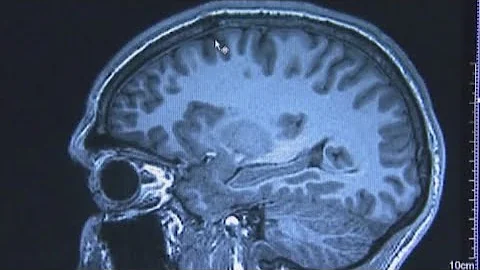

The Difference Between Alzheimer's Disease And Dementia | Ohio State Medical Center

Maria Kataki, MD, PhD, a neurologist at The Ohio State University Medical Center, discusses the difference between Alzheimer's ...